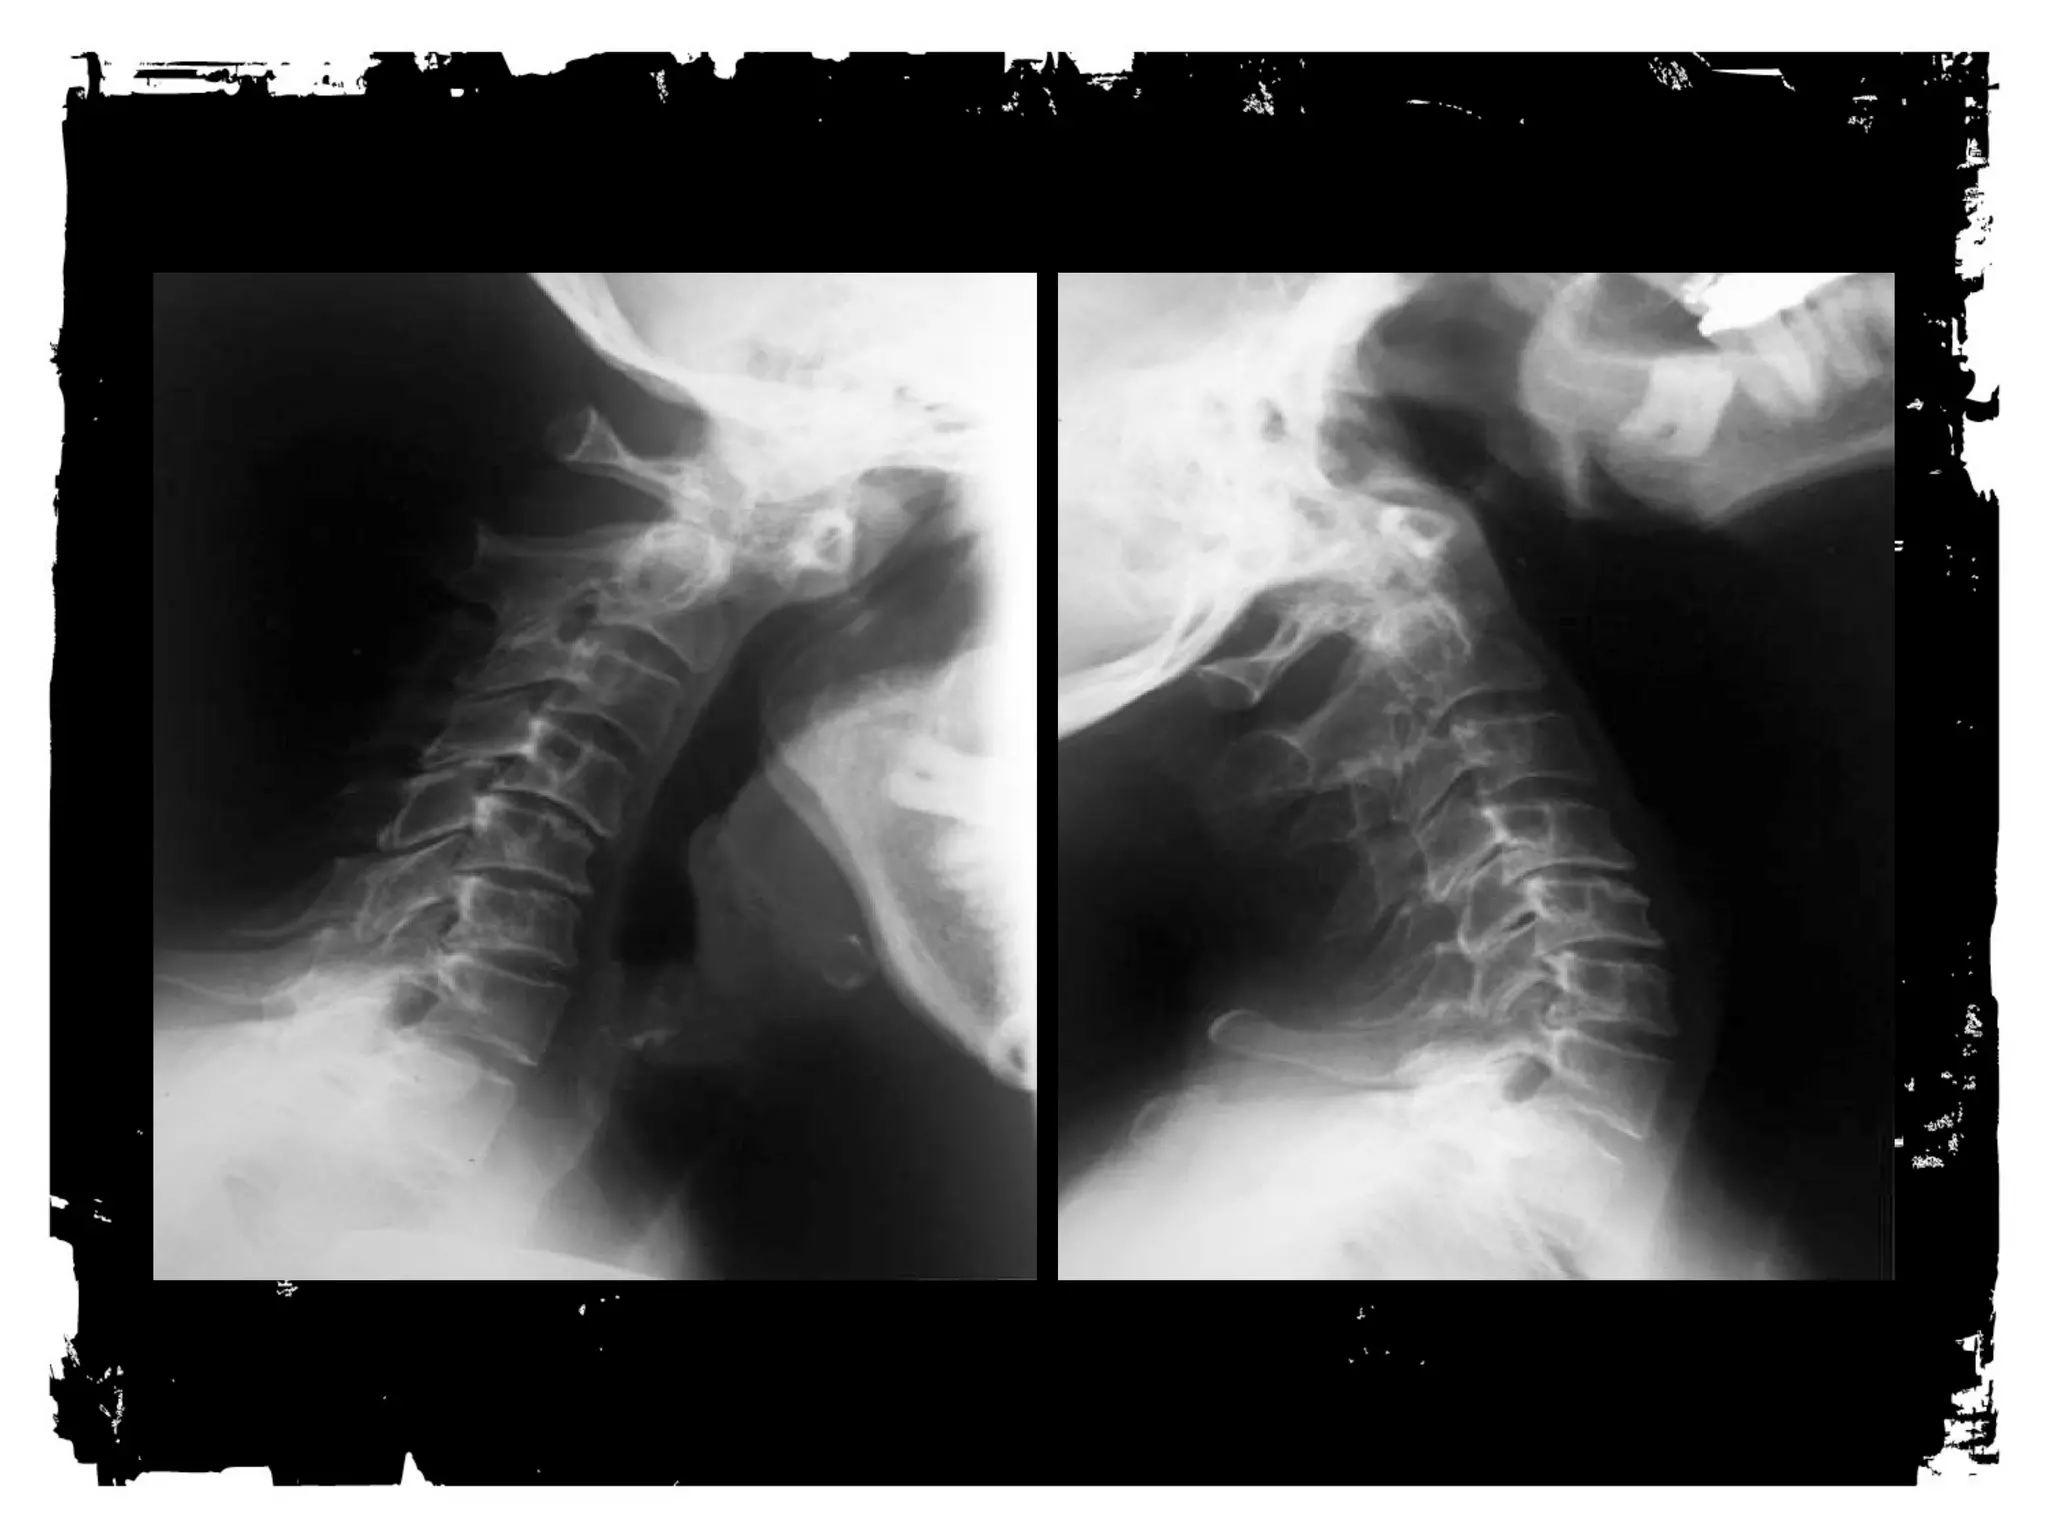

RADIOGRAPHY for primary cervical spine

screening

• Minimum standard views

– Lateral through C7

– AP

– Odontoid

• Supplementary views

• Bilateral obliques

– Swimmer’s

– Flex ion and extension

Lateral View

Base of the occiput should be visualized

Junction of C7-T1 must be visualized

A swimmer’s view taken with one arm extended over

the head can be helpful

AP view

Must include the spinous processes of all the cervical

vertebrae from C2 trough T1.

OM view

Must show relationship of the lateral masses of C1

and the odontoid process.

NNOORRMMAALL CCEERRVVIICCAALL SSPPIINNEE

1 = anterior vertebral line

2 = posterior vertebral line

3 = spinolaminar line

4 = posterior spinous line

CCeerrvviiccaall SSppiinneess NNoorrmmss

PPrreeddeennttaall ssppaaccee • 3mm or less

(4-5mm in children)

CC22--CC33 ppsseeuuddoossuubblluuxxaattiioonn • 3mm or less

RReettrroopphhaarryynnggeeaall ssppaaccee • < 6mm at C2

• < 22mm at C6

• For children 1/2 to 2/3

vertebral body distance

anteroposteriorly

AAnngguullaattiioonn ooff ssppiinnaall ccoolluummnn aatt

aannyy ssiinnggllee iinntteerrssppaaccee lleevveell

• < 11 degrees

CCoorrdd ddiimmeennssiioonn • 10-13mm

Case 1

CLICK HERE TO ADD TEXT